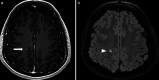

The recently developed effective treatment of primary progressive multiple sclerosis (PPMS) requires the accurate diagnosis of patients with this type of disease. Currently, the diagnosis of PPMS is based on the 2017 McDonald criteria, although the contribution of magnetic resonance imaging (MRI) to this process is fundamental. PPMS, one of the clinical types of MS, represents 10%-15% of all MS patients. Compared to relapsing-remitting MS (RRMS), PPMS differs in terms of pathology, clinical presentation and MRI features. Regarding conventional MRI, focal lesions on T2-weighted images and acute inflammatory lesions with contrast enhancement are less common in PPMS than in RRMS. On the other hand, MRI features of chronic inflammation, such as slowly evolving/expanding lesions (SELs) and leptomeningeal enhancement (LME), and brain and spinal cord atrophy are more common MRI characteristics in PPMS than RRMS. Nonconventional MRI also shows differences in subtle white and grey matter damage between PPMS and other clinical types of disease. In this review, we present separate diagnostic criteria, conventional and nonconventional MRI specificity for PPMS, which may support and simplify the diagnosis of this type of MS in daily clinical practice.